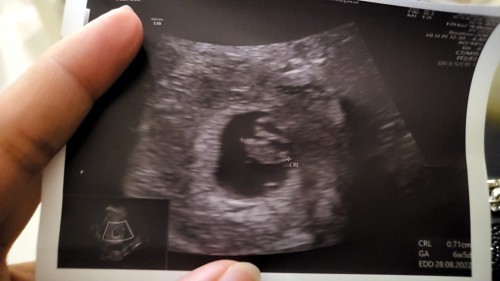

ท่านใดเคยตรวจครั้งแรก เจอหัวใจน้อง และ ครั้งที่สองไม่เจอหัวใจไหมค่ด.. โอกาสทีน้องจะรอดมีไหม